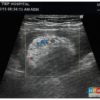

Lồng ruột

» Thông tin: Nam giới – 75 tuổi.

» Lâm sàng: Đau hố chậu phải + Bí trung tiện.